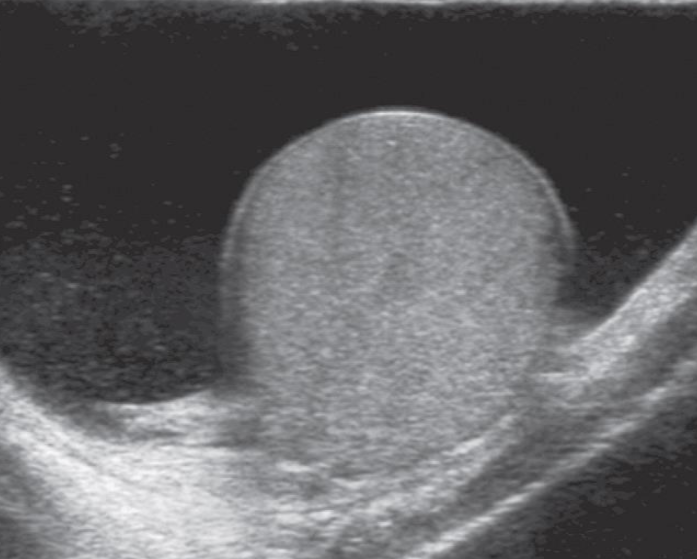

A. Give the name of imaging examination.

Color Doppler ultrasound of both testes (transverse plane) of a 14-year-old boy

B. Describe the abnormality woke up with acute right scrotal pain - The right testis shows intratesticular flow slightly reduced compared to the left testis

C. What is the most probable diagnosis ? These findings are consistent with testicular torsion